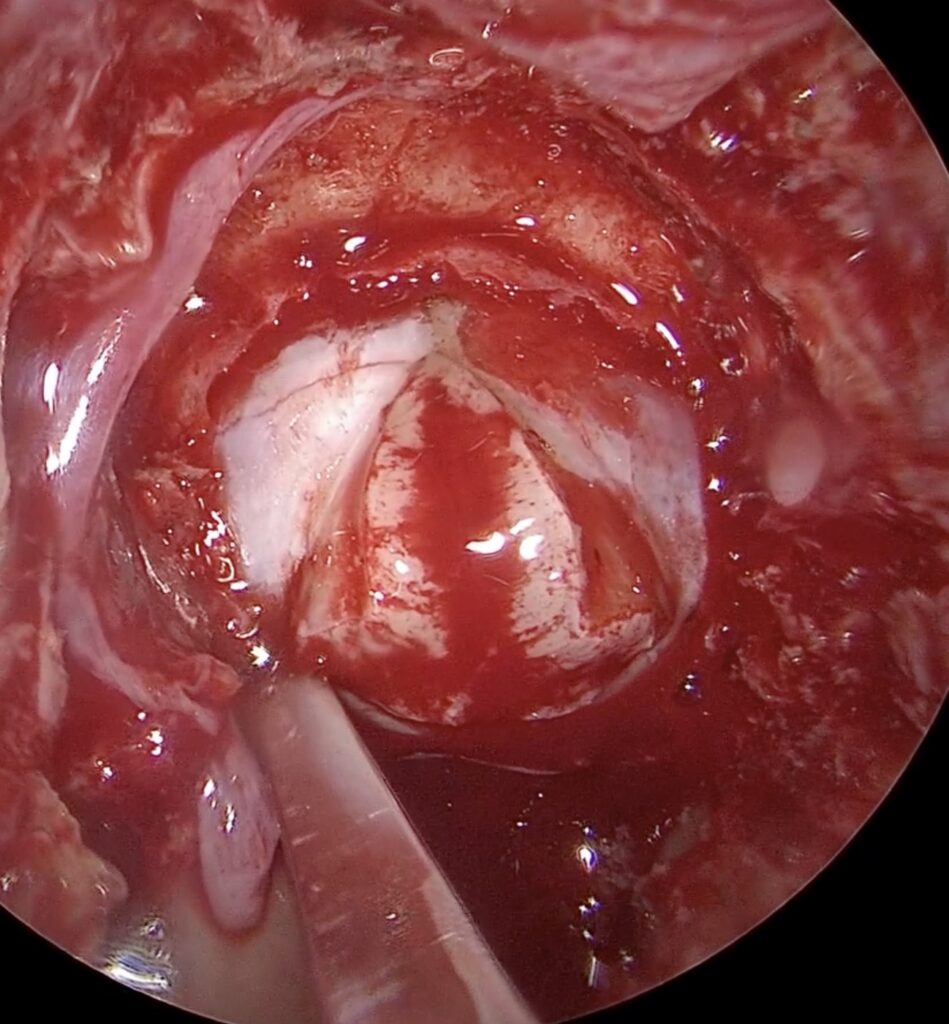

37歳女性 下垂体線腫を内視鏡手術しました。両耳側の視野欠損が回復しました。

若いですが、視野狭窄で発見された下垂体線腫を内視鏡で摘出しました。トルコ鞍前壁を十分に削除することで、上方の腫瘍残存をなくし、術後出血を防止できました。一過性に尿崩症が出現しましたが、コントロールされ退院されました。